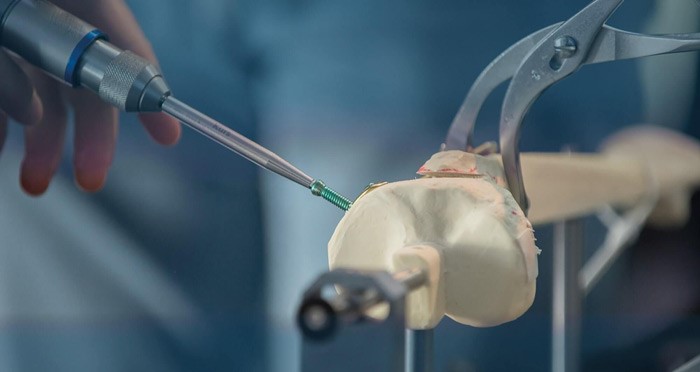

استئوتومی توسط متخصص جراحی ارتوپدی، و تحت بیهوشی انجام میشود. بسته به شرایط، بیهوشی عمومی یا بیحسی نخاعی اعمال میشود. در حین عمل، جراح برش کوچکی در پوست ناحیه مورد نظر ایجاد میکند. سپس، به وسیله نوعی سیم راهنمای مخصوص، استخوان را اندازه گرفته، با اره جراحی، قطعه استخوان ناخواسته را جدا میکند. این کار در استخوان شکاف یا فضایی ایجاد میکند. جراح این فضا را به کمک پیچهای ریز و صفحات فلزی میبندد، یا توسط پیوند استخوان آن را پر میکند. استخوان پیوندی از لگن خود بیمار یا از بانک استخوان فراهم میشود. پیچ، صفحه و سایر سخت افزارهای فلزی، یا پس از بهبودی از بدن خارج میشوند، یا به طور دائمی همانجا میمانند. بسته به نوع جراحی، بیمار چند روز در بیمارستان میماند.

اکثر استئوتومیهای زانو روی استخوان درشت نی ساق پا (تیبیا) انجام میشود تا حالت قوسی آن که داخل زانو را تحت فشار قرار داده، اصلاح شود. طی جراحی، تکه کوچکی (گوه) از بیرون استخوان درشت نی برداشته میشود. سپس استخوانهای باقیمانده به هم نزدیک، و توسط صفحه فلزی و پیچ در جای خود محکم میشوند. این کار باعث نزدیک شدن استخوانهای سمت سالم، و ایجاد فضای بیشتر بین استخوانهای آسیب دیده میشود. در نتیجه، وزن بهطور یکنواخت بر زانو توزیع شده، فشار روی بخش دردناک کم میشود. جراحی 1 تا 2 ساعت طول میکشد. به این روش که رایجتر است، استئوتومی "گوه بسته" گفته میشود. در روش "گوه باز" برای پر کردن فضای خالی ایجاد شده از پیوند استخوان استفاده میشود.

جراحی استئوتومی پری استابولار (PAO) درمان موثری برای دیسپلازی مفصل لگن است. دیسپلازی مفصل لگن به دلیل تغییر شکل سوکت (استابولوم) ایجاد میشود. این مشکل گاهی ناشی از رشد ناکافی استابولوم و ناتوانی آن در مهار و حمایت سر استخوان ران (گوی) است. دیسپلازی لگن میتواند منجر به آرتروز و ساییدگی لابروم، غضروف مفصلی، استخوانها، و نهایتا ایجاد درد و محدودیت حرکتی شود. در PAO، جراح برشهایی روی استخوان انجام میدهد تا استابولوم را جابجا کرده، اتصال لگن را به شکل طبیعیتری بازیابی کند. با این کار، حرکت استخوان ران تسهیل میشود. برای تثبیت موقعیت جدید استخوانها از پیچ استفاده میشود.